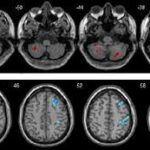

پزشکی تشخیصی در آستانه یک انقلاب بزرگ قرار گرفته است؛ فناوری نوین هوش مصنوعی قادر شده است...